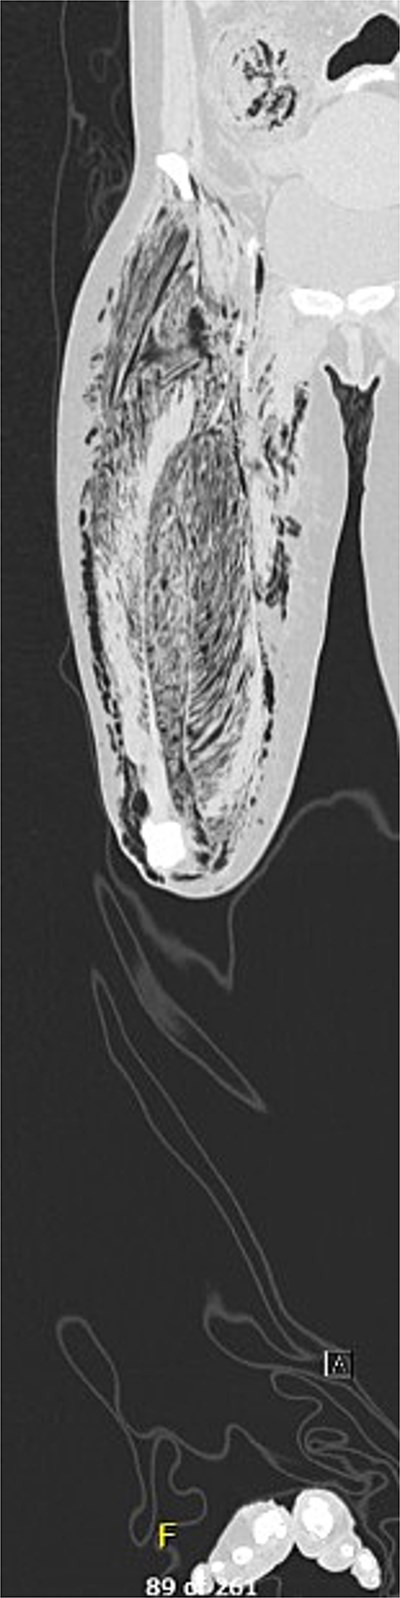

Post-operatively, the patient developed new-onset, progressive erythema and induration of the left lower extremity (LLE). Repeat CT imaging demonstrated NSTI involving the mesentery and retroperitoneum, with marked edema of intestinal and gallbladder walls. New findings included NSTI of LLE involving all tissue planes, most severe in the left gluteal musculature and thigh, and necrosis of all tissue planes of the residual RLE and pelvis. The patient was taken back to the operating room for right hip disarticulation, debridement of the LLE, and abdominal re-exploration (Fig. 3). The patient also underwent bilateral salpingo-oophorectomy and cholecystectomy given the ischemic-appearing nature of both organs. While the patient continued to improve, after a multidisciplinary discussion, an end ileostomy with abdominal closure was eventually performed due to ongoing vasopressor requirement. She was eventually extubated, weaned off sedation, and downgraded to the surgical ward. The patient ultimately recovered well throughout the remainder of her hospital stay.